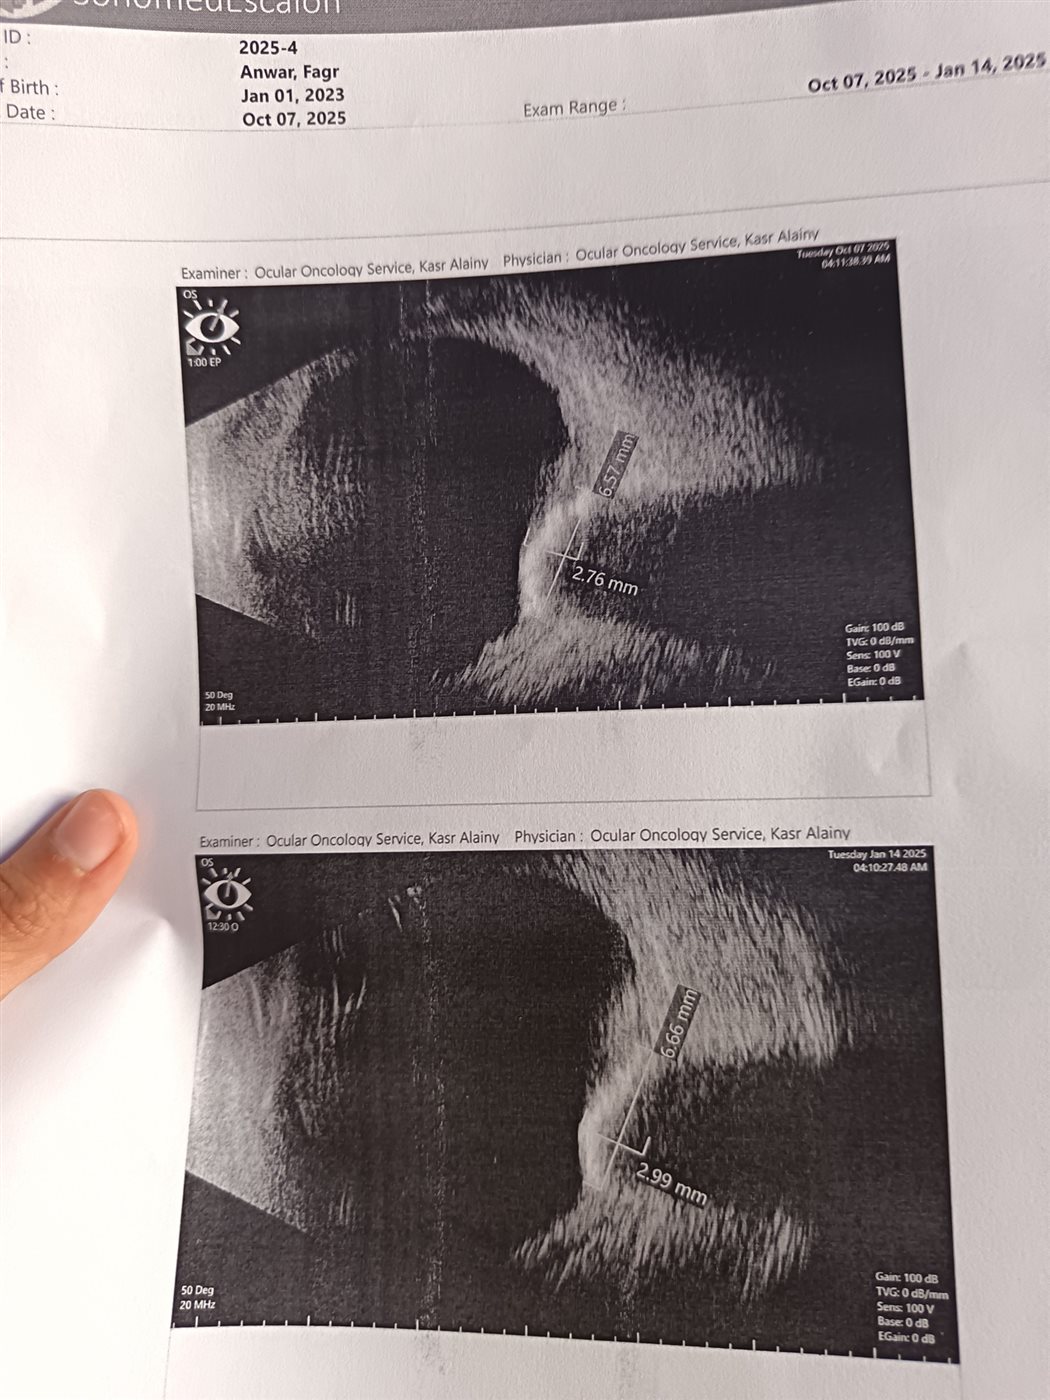

وأشارت إلى أن فريق طبي في الإسكندرية أوصى باستخدام العلاج الكيميائي عبر القسطرة الشريانية، وهو علاج دقيق يتم من خلال حقن الدواء مباشرة في الشريان المغذي للعين، إلا أن الفحص الأخير أكد عدم إمكانية إجرائه حالي بسبب تفاقم الحالة، ليبدأ الصغير دورة جديدة من العلاج الكيميائي بجرعات مضاعفة، ورغم تلقيه الجرعة الثانية، أكدت تقارير المتابعة أن الأورام لم تستجب للعلاج، وأن النزيف الداخلي ازداد، ما دفع أطباء الأورام إلى الإشارة بأن بقاء العين أصبح مهدد بشكل كبير، وأن استئصالها قد يكون الخيار الطبي الأقرب.